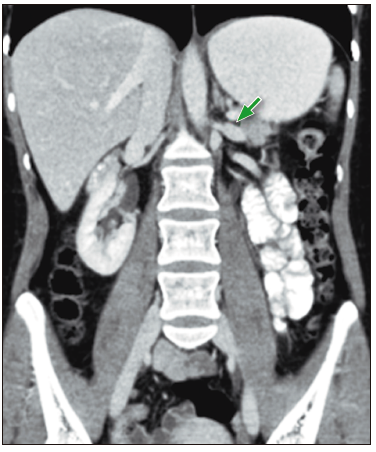

Figura 4. En el corte coronal de la TC de abdomen con contraste, se observa la

dilatación retrograda de la vena renal izquierda